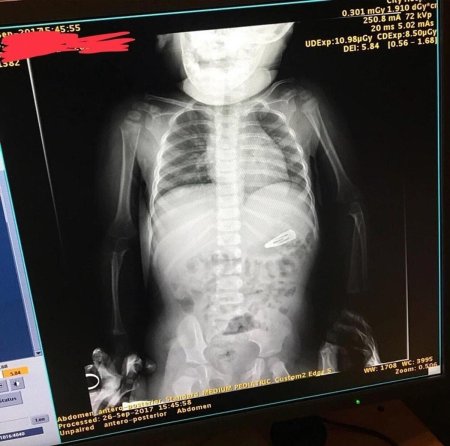

Рентгеновский эффект создает фантастические композиции в этих фотографиях девушки, чье тело становится прозрачным, демонстрируя скелет и внутренние органы. Она позирует в разных позах, ее силуэт светится загадочным свечением. Каждый кадр передает атмосферу научной фантастики и медицинского искусства. Ее кожа кажется полупрозрачной, позволяя увидеть кости и мышцы. Фотографии рассказывают о хрупкости человеческого тела и его внутренней красоте. Девушка то стоит в задумчивости, то делает грациозное движение. Эти иллюстрации вдохновляют на размышления о человеческой анатомии и уязвимости. Каждая картинка - это момент прозрения, когда внешнее уступает место внутреннему. Девушка воплощает образ современной Медузы, сочетающей красоту и загадочность.

Сквозь материю: тайны анатомии